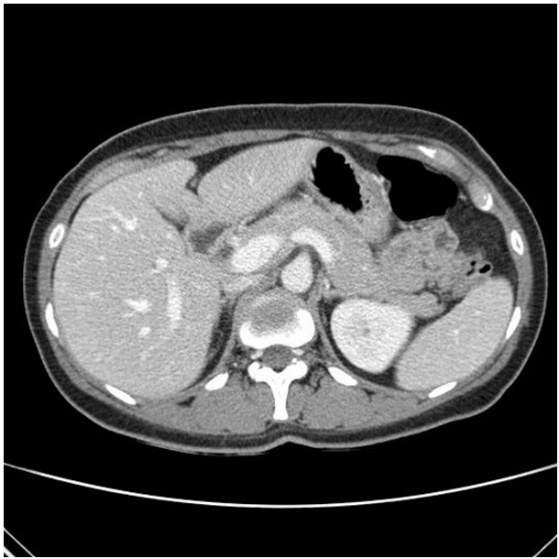

One hour after arrival at the emergency room, the patient underwent abdominal and pelvic CT scan, which revealed a copious amount of hemorrhage in the abdomen and multiple intra-abdominal organs (liver, stomach, small and large bowel, and uterus) protruding through the large anterior abdominal wall defect, suggesting hernia (Figure 1). Her severe abdominal pain did not resolve even with opioid analgesics. The authors discussed with the department of general surgery regarding the large ventral hernia and the possibility of strangulation, and suspected that the severe pain might not be related to strangulation, but tears in the abdominal wall muscles. Since her vital signs were soon stabilized with hydration and there was no evidence of strangulation, the authors decided to monitor the patient closely rather than carry out an emergency operation. The patient’s hemoglobin level decreased to 7.5 g/dL by one and a half hours, and was transfused with PRC 1200 cc. The hemoglobin level increased up to 10.4 g/dL, following transfusion.

Figure 1.

Figure 1.— Liver (left), stomach, small and large bowel (right) protrusion through the abdominal wall defect on the computed tomography.